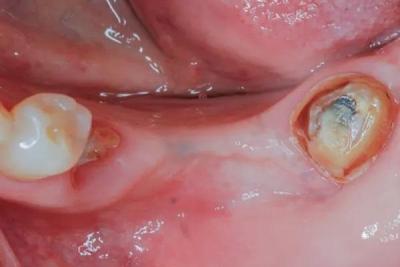

Направленная костная регенерация (НКР) требует стабильного комплекса трансплантат-мембрана. В этой статье представлена новая техника, в которой винты для фиксации мембраны служат в качестве анкеров для стабилизирующих мембрану швов без необходимости рассечения надкостницы и прокалывания буккоапикальной надкостницы. Эта методика может быть жизнеспособной альтернативой, если Вы хотите избежать сложностей, связанных с наложением периостальных швов и прямой фиксацией мембраны с помощью пинов или винтов. Эта методика, в которой анкерные винты используются в качестве опорных линий, может применяться во время удаления зуба, а также для наращивания гребня беззубого участка при подготовке к будущей установке дентальных имплантатов. Представлены два случая, в которых показана осуществимость этой техники, при которой целостность и стабильность рассасывающейся мембраны сохраняется до окончательного ушивания, что позволяет предположить, что винты, используемые в качестве якорей для стабилизирующих швов, могут быть предсказуемым вариантом при устранении сложных горизонтальных дефектов, требующих НКР.